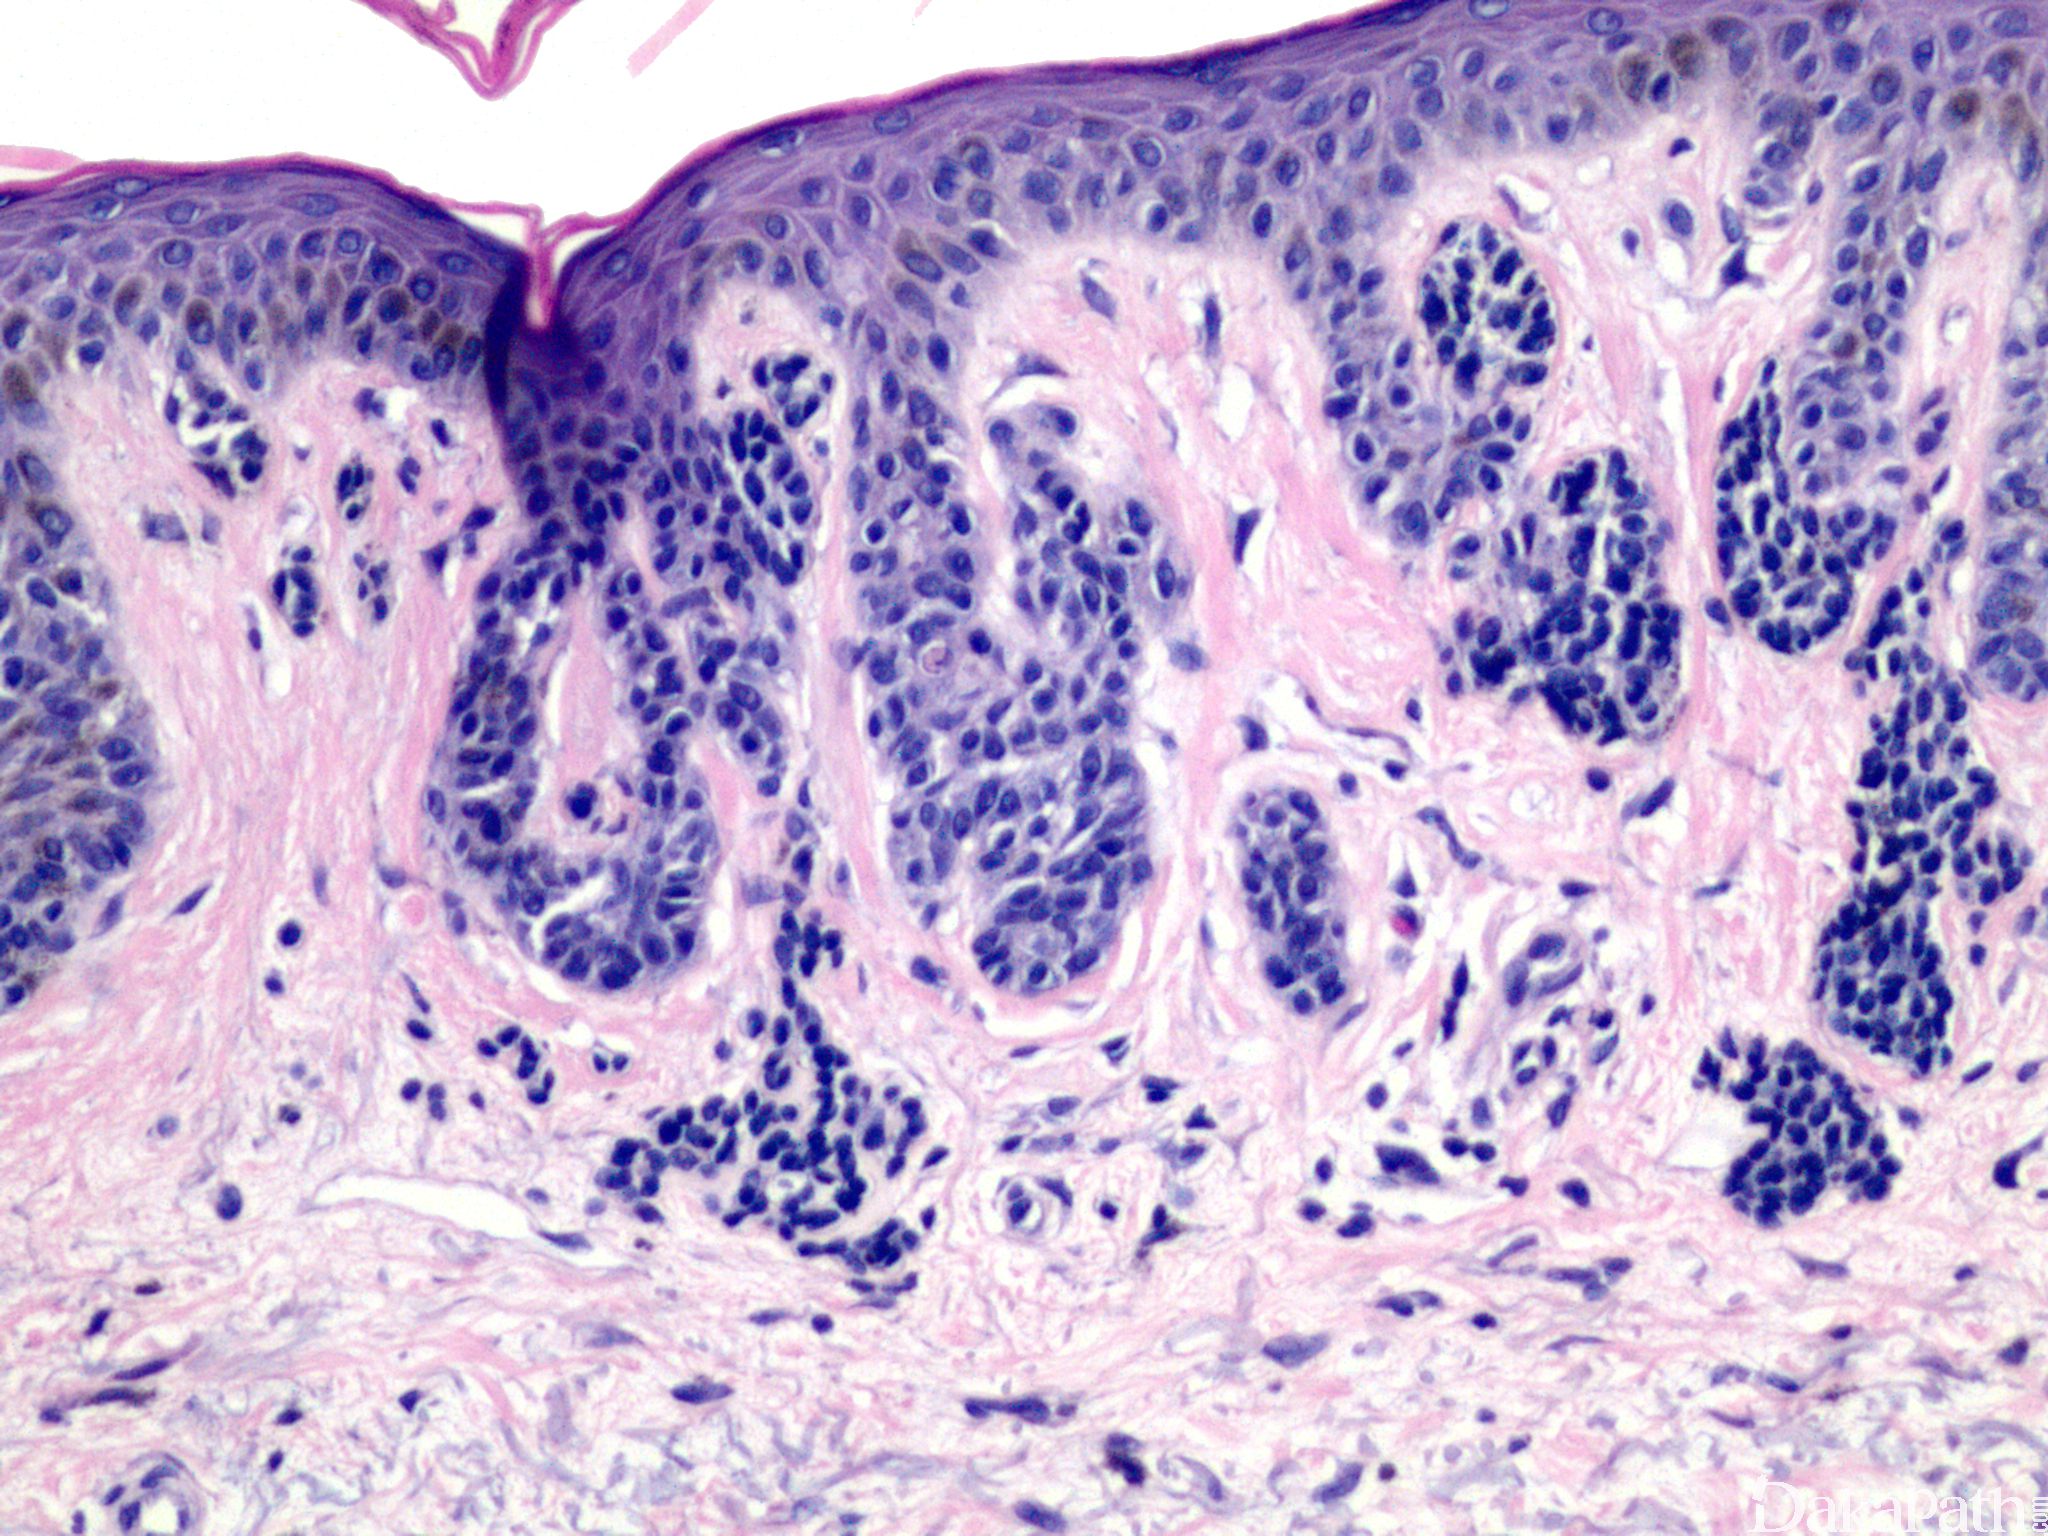

色素细胞增生限于表皮的基底层(与真皮交界处)。

3. 表皮基底层圆形痣细胞巢,常起源于上皮脚尖端,部分表现为水滴样突入真皮;

4. 多少不等的雀斑样色素细胞增生;

5. 细胞形态温和,无异型及核分裂像。